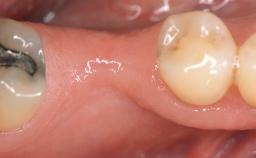

Adequate peri-implant soft-tissue thickness is essential not only for esthetic but also for functional reasons. In this case, Vincenzo Iorio Siciliano demonstrates how he achieved increased height and thickness of posterior peri-implant soft tissues to obtain a stable mucosal seal and a width of keratinized tissue favorable to toothbrushing.

The patient, a healthy 38-year-old woman, was referred for increasing the width of the keratinized tissues at the buccal aspect of dental implant 46. The site exhibited a premature-closure screw exposure caused by trauma during chewing, with inadequate keratinized tissue.